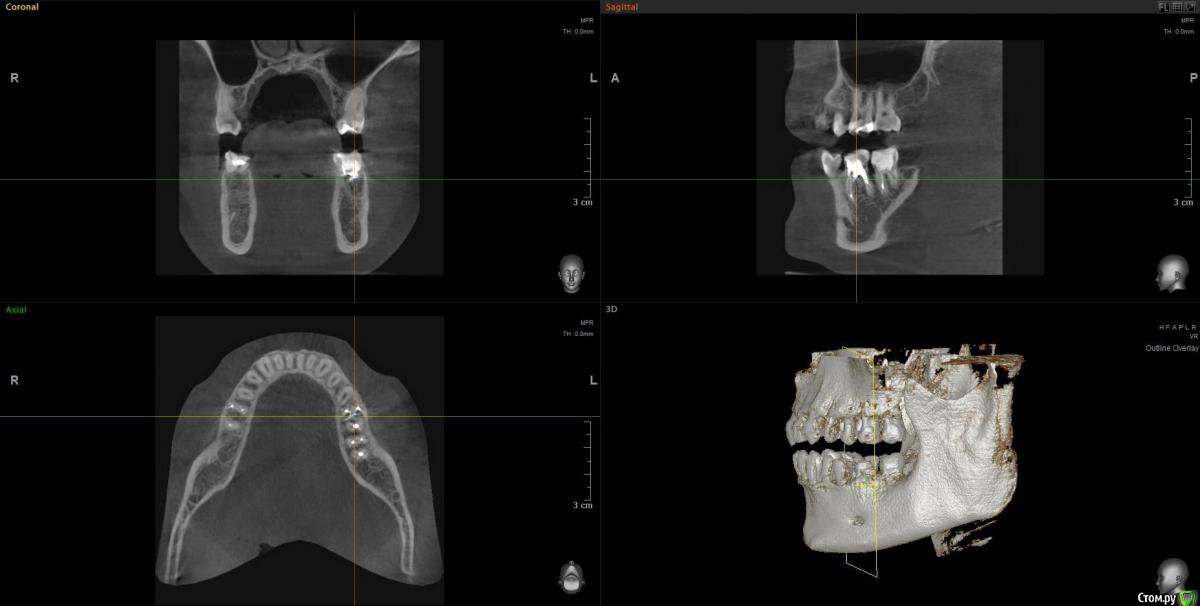

Vords Опубликовано 11 июня, 2020 Поделиться Опубликовано 11 июня, 2020 (изменено) Доброго вечера, профессионалы. Прошу у Вас помощи. Буду очень благодарен за консультацию. 3 недели назад появились боли в в жевательных зубах (около 37 и 36 зубов). В виду того, что боли были достаточно серьезные, а врач, у которого я лечился ранее не мог меня принять из-за пандемии - пришлось идти в городскую поликлинику. По результатам похода был поставлен диагноз пульпит 37 и глубокий кариес 36. На 36 поставили пломбу - 37 успешно депульпировали. На этом история 37 зуба закончена. С 36 после постановки пломбы начались дикие ночные боли и боли при накусывании. На повторном приеме был поставлен диагноз пульпит 36 - поставлено лекарство для умертвления нерва. После этого боль при накусывании прошли. В следующий прием пришел на чистку каналов и пломбировку. Во время этой процедуры я вдруг ощутил совершенно дикую боль (как выяснилось потом - в этот момент и произошла перфорации в области фуркации). Врач ничего не сказал - просто поставил метапекс и запломбировал каналы. В этот момент начались боли при накусывании. а потом постоянная тянущая боль. Продолжалось это около 3 дней - я пошел в другую стоматологию где мне сделали рентген и с подозрение на перфорацию отправили на КТ. По результатам КТ перфорация была подтверждена. С КТ я пришел в городскую стомотологию где мне предложили закрыть перфорацию цементом (pro что-то там - не могу сказать точно). Закрыли ее во вторник на этой неделе. Сегодня восстановили коронку и поставили световую пломбу. Беда в том, что боль при накусывании и "нытье" с этой стороны так и не прошли. По словам стомотолага гос клиники - боль при накусывании из-за метапекса и когда он рассосется - боль пройдет. (до 6 месяцев). Я прилагаю рентген (ужасное качество), фото КТ и ссылку в облако на КТ. Я допускаю, что никто не захочет лезть в облако и тратить свое время на просмотр на КТ (сам не могу разобраться с программой, что бы сделать достойные скрины), но если вдруг у кого-то найдется время - буду очень благодарен. Рентген сделан сразу после пломбировки канала. КТ через 3 дня после этого. В связи с этим вопрос. Возможно ли, что боль при надавливании пройдет если подождать пока рассосется метапекс или это пустая трата времени? Мне стоит ждать какое - то время или в этой ситуации мне поможет только удаление? Благодарю Вас за уделенное время Ссылка на КТ https://cloud.mail.ru/public/44WE/2JeTfXmr2 Изменено 11 июня, 2020 пользователем Vords Ссылка на комментарий

wladdX Опубликовано 11 июня, 2020 Поделиться Опубликовано 11 июня, 2020 (изменено) Скриншоты Изменено 11 июня, 2020 пользователем wladdX 1 Ссылка на комментарий

Vords Опубликовано 11 июня, 2020 Автор Поделиться Опубликовано 11 июня, 2020 (изменено) WladdX, огромное спасибо Вам за потраченное на скрины время. А то я так и не смог освоить эту программу (рукалицо). У меня даже есть ощущение, что я вижу теперь штифт, о котором говорил krokomot (хотя и не факт)))) Изменено 11 июня, 2020 пользователем Vords Ссылка на комментарий